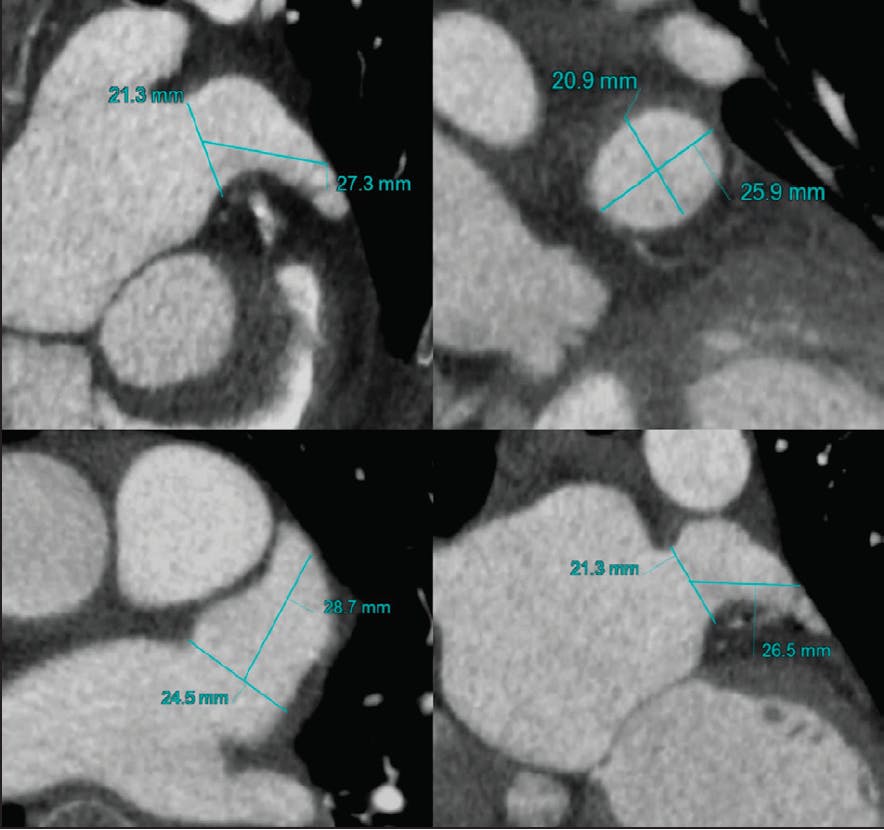

Transesophageal echocardiography (TEE) remains the most commonly used imaging modality to plan for and guide LAAO worldwide (Figure 1). However, there is a growing interest in cardiac CTA (CCTA) for preprocedural planning and postprocedural surveillance (Figure 2).2,3 Regardless of the chosen imaging modality, the essential data needed by the interventionalist to achieve safe and efficient LAAO include determinants of LAA suitability for closure and predictors of a challenging LAA procedure (Table 1).

Figure 2. Sizing of the LAA for implanting a Watchman device using CCTA.

LAA sizing.  The diameter and depth of the LAA are the two most important elements needed for anatomic suitability screening. Unfortunately, there is considerable variability in measuring and reporting those dimensions in clinical practice. For example, an LAA with an acute chicken wing anatomy may be reported to have a 32-mm depth, but only 16 to 18 mm of this depth can be used to perform the LAAO procedure. Similarly, the ostial diameter is commonly measured at a different location than the intended landing zone for the specific device. Although several landmarks can be used to report those dimensions (eg, left circumflex coronary artery), the best ostial and depth measurements for the procedure are those that are performed by an interventional imager who is (1) familiar with the LAAO devices used in their interventional lab and (2) able to envision/simulate device deployment while performing the screening imaging. Essentially, the operator needs to know if the LAA is amenable for closure with a certain LAA occluder. Published sizing criteria can be a useful guide to determine suitability for LAA closure4; however, they cannot replace the foresight of an experienced interventional imager who can simulate the implant either conceptually or with the use of advanced imaging techniques (three-dimensional [3D] TEE reconstruction, 3D printing, or CCTA simulator software).